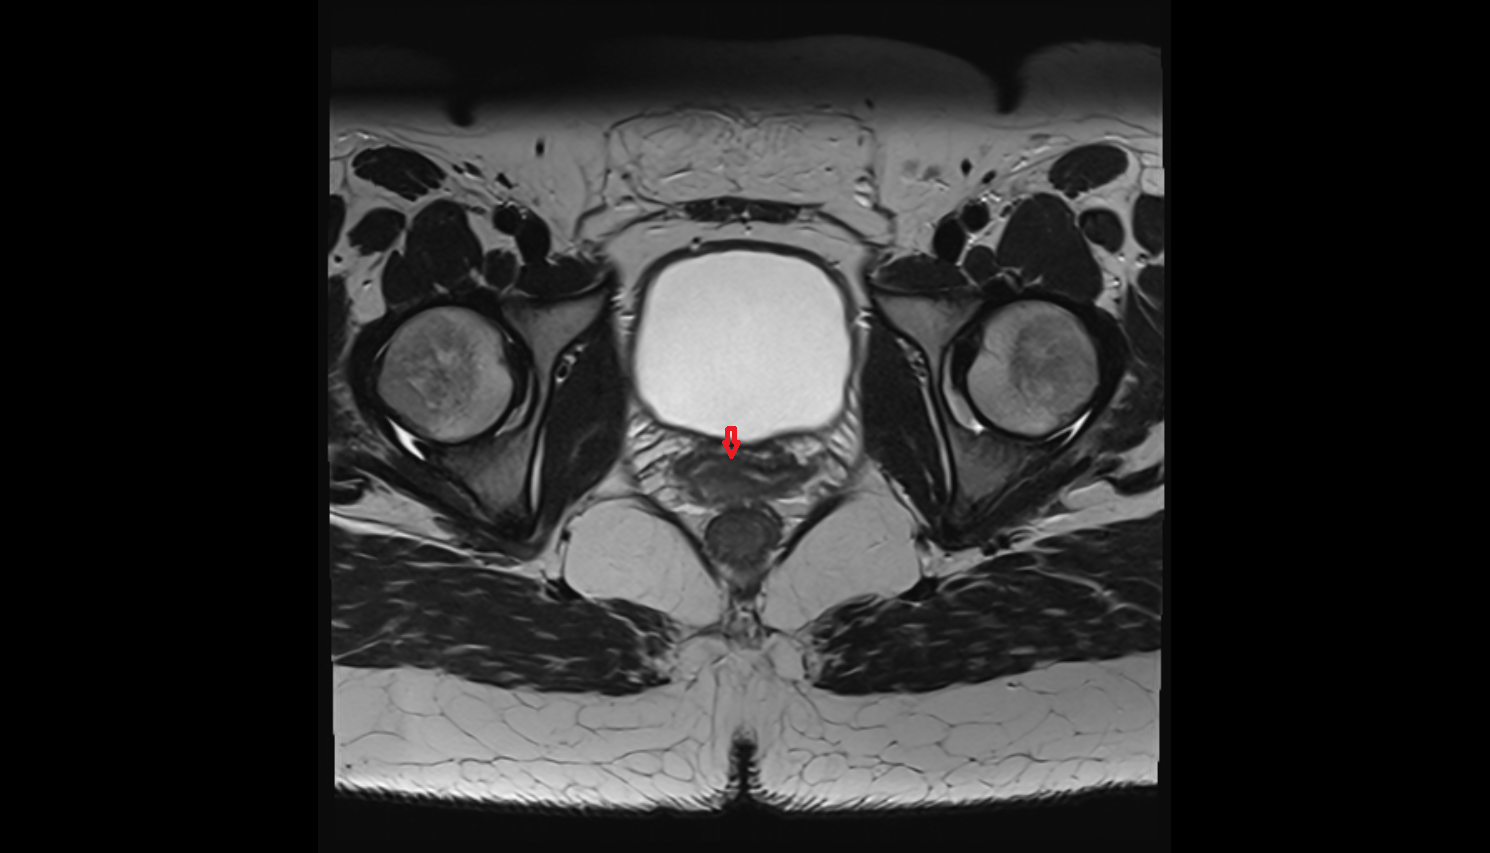

- Urinary bladder

- Uterus

- Pubic symphysis

- Rectum

- Levator ani muscle

- Obturator internus muscle

- Peripheral zone of prostate

- Anterior Fibromuscular Stroma of prostate

- Central zone of prostate

- Transitional zone of prostate